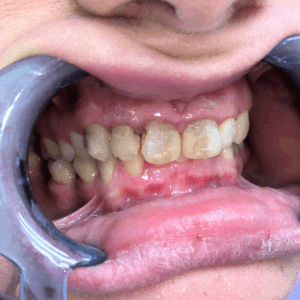

Pacijent 1